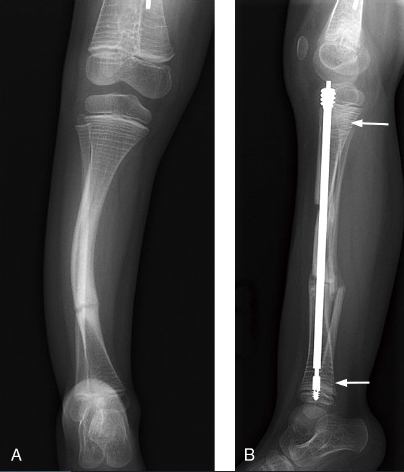

要診斷典型的OI並不困難,當病人有多處或多次骨折且鞏膜呈藍灰色時,即可做臨床診斷。但目前的醫療還沒辦法完全治癒OI。目前為止並無完全治癒先天性成骨不全症的方法,臨床上以支持性療法為主:即預防骨折、使用輔助器協助患童的日常活動、骨折的非手術治療包括短期副木來降低失用性骨質缺乏的可能和預防循環性骨折。因為孩子的骨頭是很小,且骨髓腔很窄,一般的鋼板根本打不上,加上骨頭很鬆,螺絲打進去很容易就鬆掉。所以,最好採骨髓內釘(圖一),固定在骨髓裡頭,才不容易再發生骨折的情形。但是,採取此種手術治療的話,孩子會長大,等到兒童骨骼成長到一段時間之後(約三至四年),就必須更換較長的骨髓內釘。